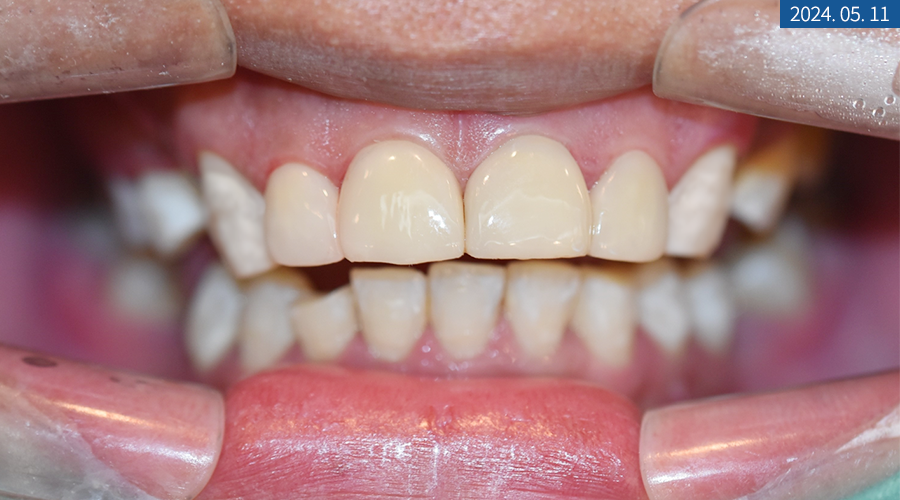

마무리된 앞니를 보면 전과 다르게 깨지고 갈라진 크랙 없이 단정하고 밝은 느낌이 들게 되었습니다.

환자분도 현재 음식을 가리지 않고 잘 섭취하고 있다는 등 만족스럽다는 말씀을 주셨는데요.

특히 전치부를 친구들이 보면서 어디서 했냐고 물어본다고 하셨답니다^^